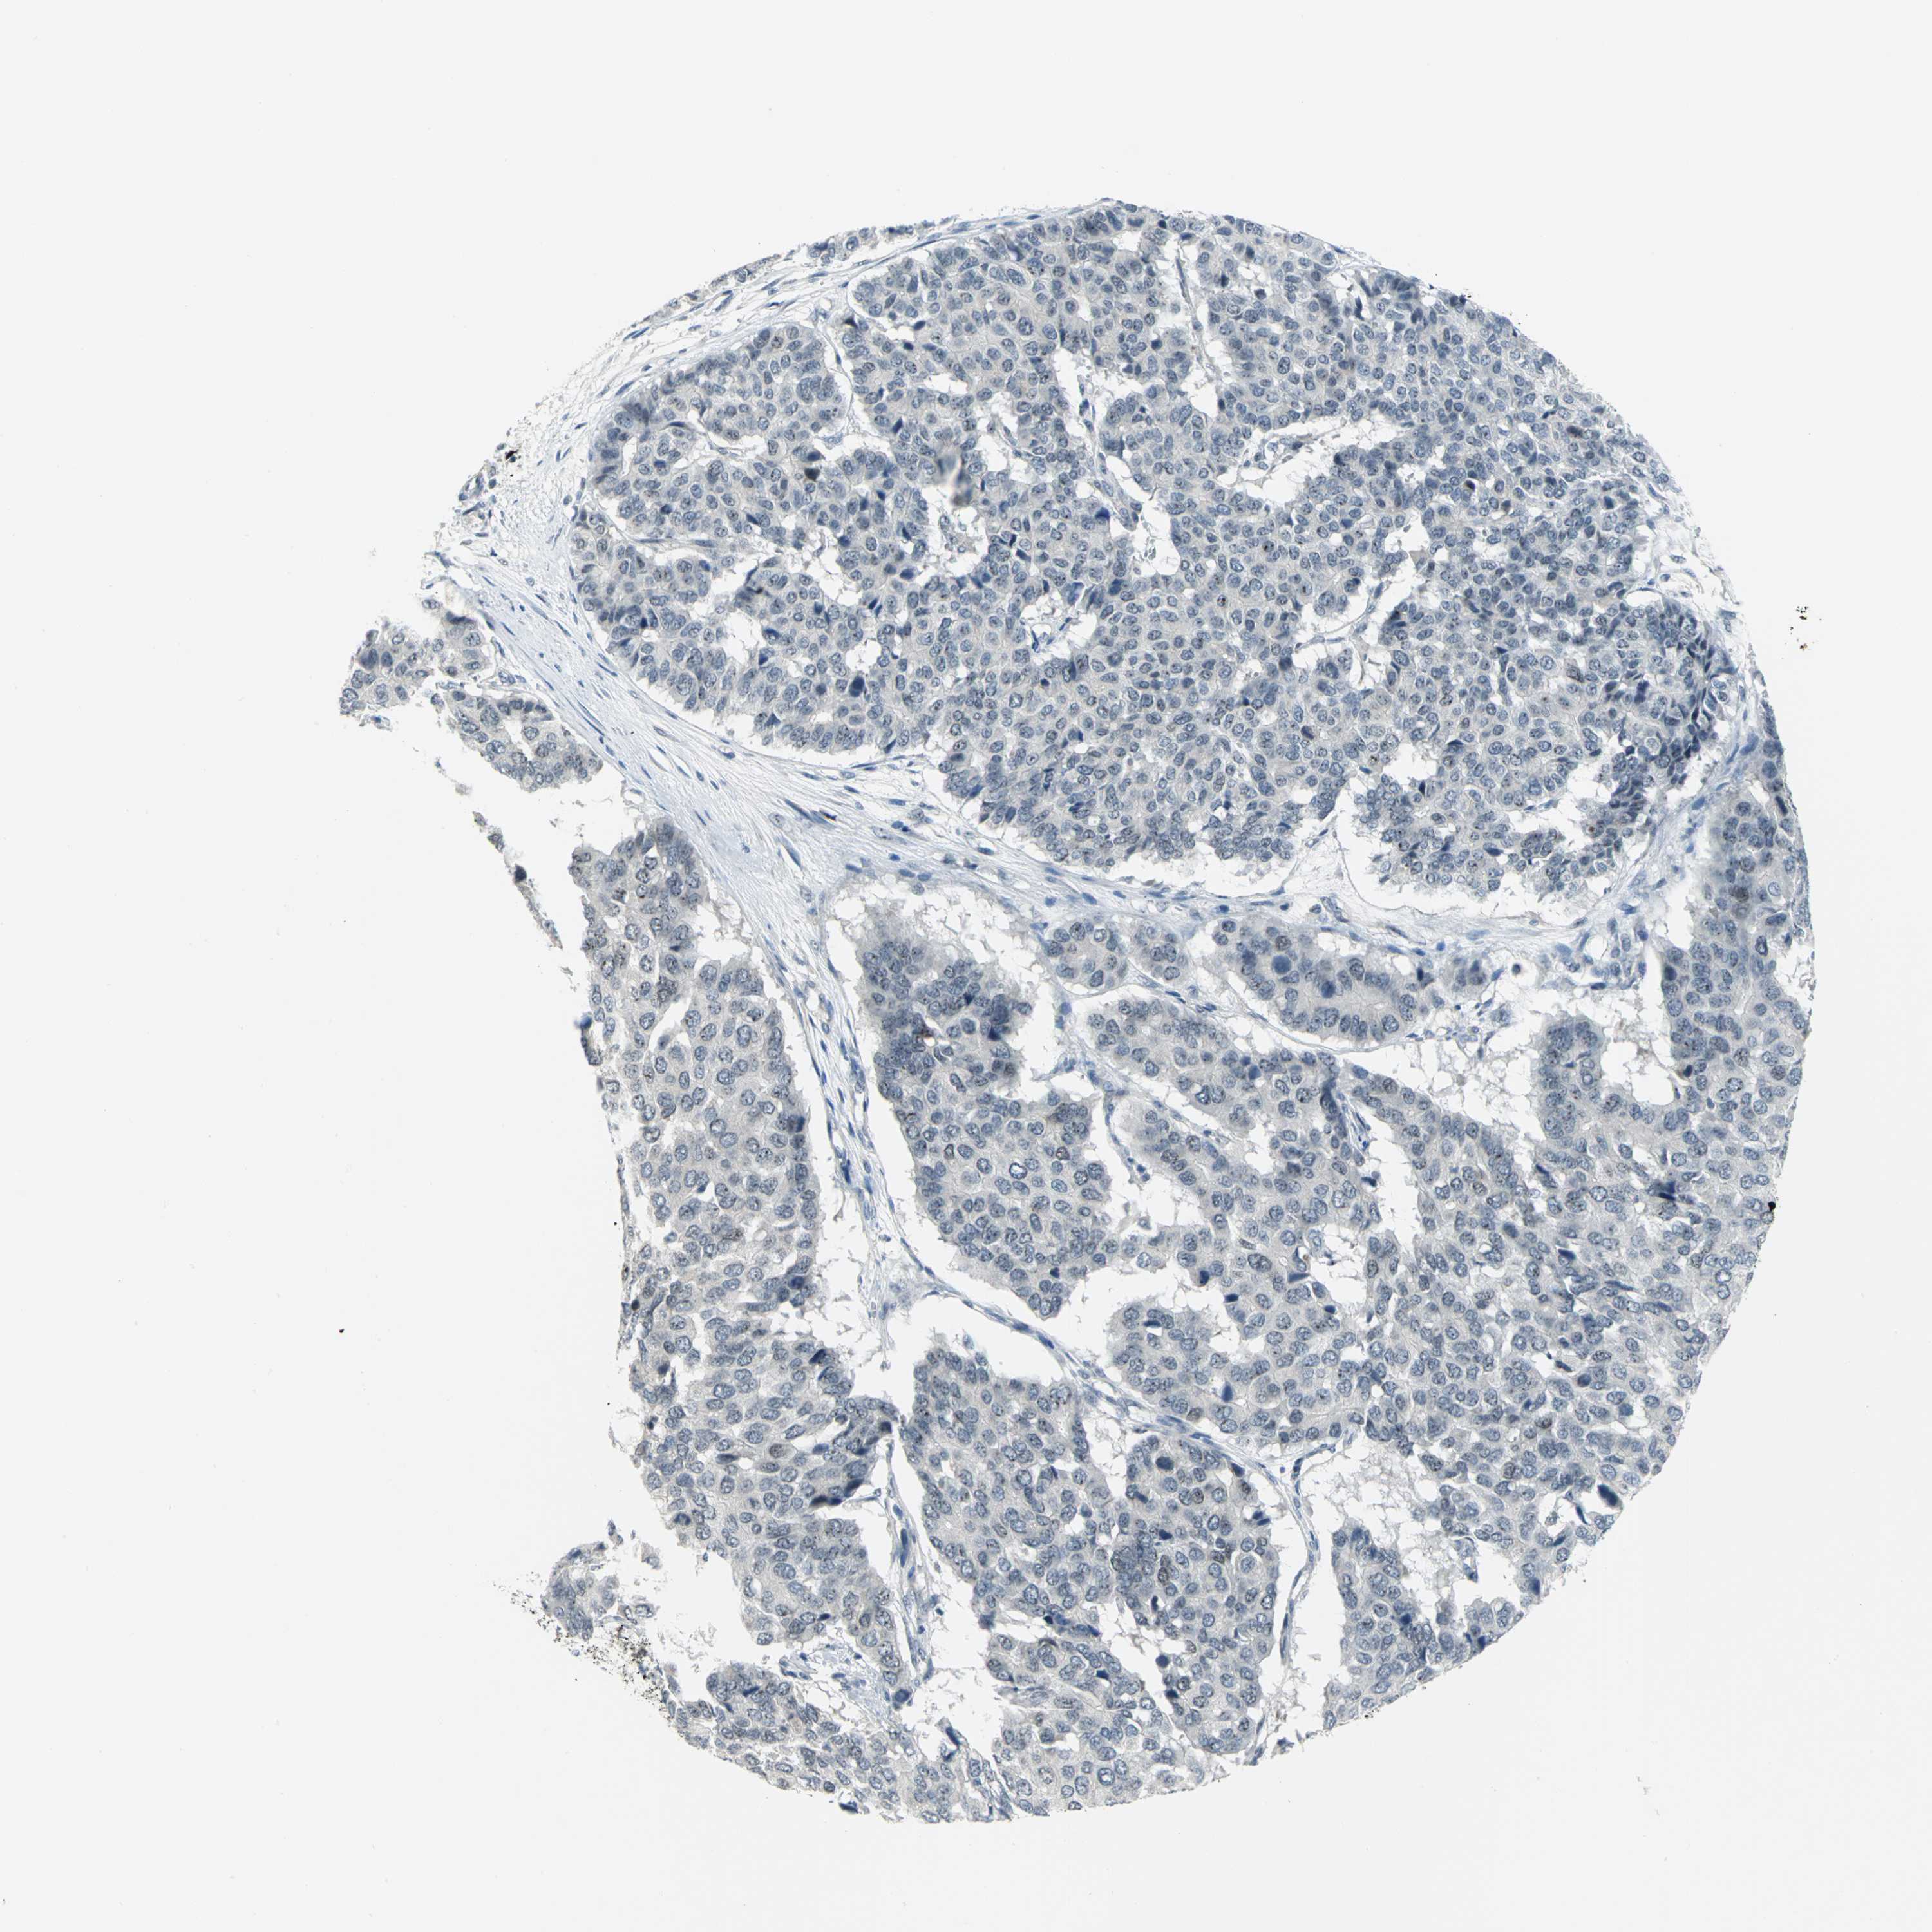

PANCREATIC CANCER - Protein expressioni

A mouse-over function shows sample information and annotation data. Click on an image to view it in a full screen mode. Samples can be filtered based on level of antibody staining by selecting one or several of the following categories: high, medium, low and not detected. The assay and annotation is described here.

Note that samples used for immunohistochemistry by the Human Protein Atlas do not correspond to samples in the TCGA dataset.

Antibody stainingi

Antibody staining in the annotated cell types in the current human tissue is reported as not detected, low, medium, or high, based on conventional immunohistochemistry profiling in selected tissues. This score is based on the combination of the staining intensity and fraction of stained cells.

Each image is clickable and will lead to virtual microscopy that enables deeper exploration of all samples and also displays staining intensity scores, fraction scores and subcellular localization as well as patient and tissue information for each sample.

Antibody HPA005466

Staining

High

Medium

Low

Not detected

Intensity

Strong

Moderate

Weak

Negative

Quantity

>75%

75%-25%

<25%

None

Location

Nuclear

Cytoplasmic/membranous

Cytoplasmic/membranous,nuclear

Adenocarcinoma, NOS

Adenocarcinoma, metastatic, NOS